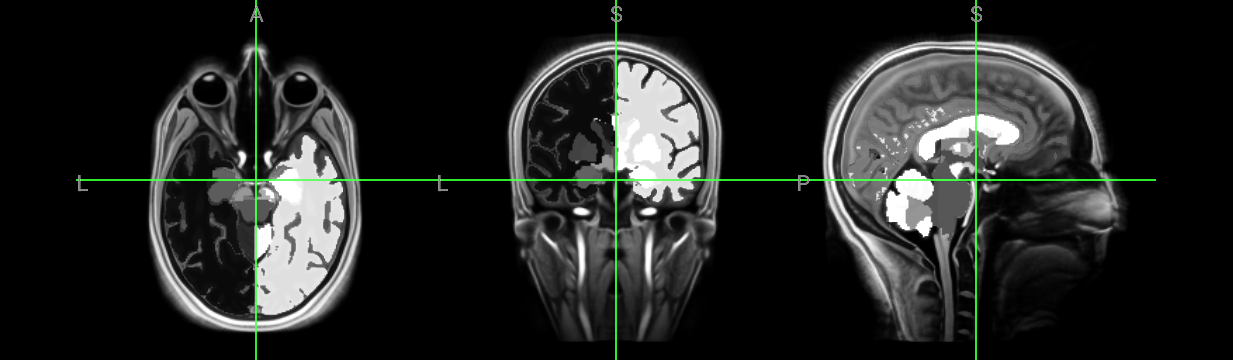

MP2RAGE T1-weighted average 7T model (human brain model)

• Bollmann, Steffen, Andrew Janke, Lars Marstaller, David Reutens, Kieran O’Brien, and Markus Barth. “MP2RAGE T1-weighted average 7T model” January 1, 2017. doi:10.14264/uql.2017.266